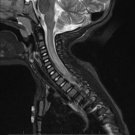

Nicholas V. Mendez, BS; Ayman M. Salah, PhD; Kelsey A. Musgrove, BS; Syed A.A. Rizvi, PhD, MBA; Sultan S. Ahmed, MD; Jasmin Ahmed, BS, MS, MD

​A 33-year-old woman with no significant past medical history presented to our family medicine practice with concern for a headache when she laughs or leans her head forward.

10/29/2019